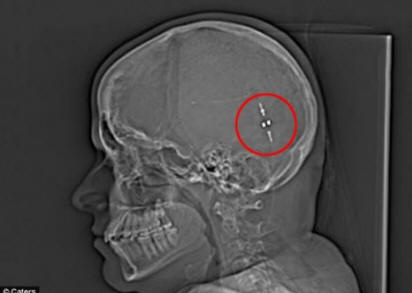

Mutta sen jälkeen kun he löysivät tavan poistaa ylimääräinen neste hänen aivonsa mahaan, hänen elämänsä on muuttunut. Valuta, joka tunnetaan myös nimellä maha-vatsakalvon sekoitus, joka yhdisti aivot ja vatsan, mahdollistaen sen sulattaa aivojen neste ja vähentää aivojen painetta.

Ja vasta viime vuoden toukokuussa tytölle annettiin shuntti tyhjentää ylimääräinen neste. Sam toivoi välitöntä helpotusta, mutta vie hänen vartaloonsa aika tottua vieraaseen kehoon. Jonkin ajan kuluttua Samin aivot ovat sopeutuneet muutokseen siitä lähtien sitten hän elää jälleen normaalia elämää. Elämän aika